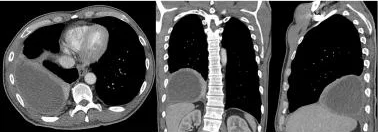

2. 胸部CT扫描

胸部CT增强扫描可增强胸膜表面,有助于描绘积液位置。

图3 胸部CT扫描显示左侧包裹性胸腔积液和脏层胸膜对比增强,表明病因可能是脓胸。

图4 吸入性肺炎导致米勒链球菌和厌氧菌的脓胸患者。对比增强CT显示胸膜增厚、胸腔积液密度高、分房和分隔。胸腔穿刺出现恶臭脓液。

胸膜增强可见于活动性炎症和严重胸膜肺感染的患者,可能是复杂性胸腔积液或脓胸的一个征象。胸部增强CT示胸膜分裂征,常见于脓胸,被积液分隔的双侧胸膜增强,如下图所示。